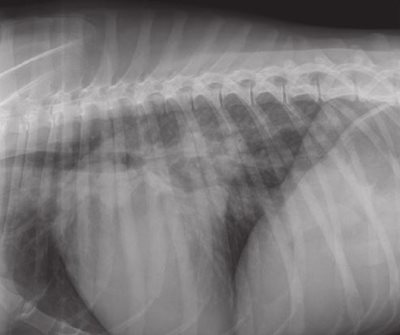

Right lateral (figure 1) and dorso-ventral (figure 2) thoracic radiographs revealed bilateral cardiomegaly (Buchanan’s vertebral scale = 13 ; normal = 9.7 +/- 0.5 [5] ; the transverse diameter was more than 2/3 of the total diameter of the thorax).

Figure 1: right lateral thoracic radiograph: left-sided cardiomegaly, venous densification, and alveolar pulmonary oedema.

Figure 2: dorso-ventral thoracic radiograph: cardiomegaly and alveolar pulmonary oedema.

The size of the left atrium was particularly increased. The tracheo- vertebral angle was decreased. Pulmonary venous densities were present on the lateral view (figure 1). The pulmonary parenchyma showed interstitial and alveolar densities consistent with alveolar pulmonary oedema (figures 1 and 2).

These radiographs confirmed the diagnosis of congestive disease with pulmonary oedema.